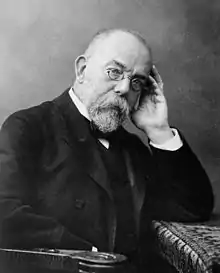

Paul Ehrlich (German: [ˈpaʊl ˈʔeːɐ̯lɪç] ⓘ; 14 March 1854 – 20 August 1915) was a Nobel Prize-winning German physician and scientist who worked in the fields of hematology, immunology, and antimicrobial chemotherapy. Among his foremost achievements were finding a cure for syphilis in 1909 and inventing the precursor technique to Gram staining bacteria. The methods he developed for staining tissue made it possible to distinguish between different types of blood cells, which led to the ability to diagnose numerous blood diseases.

In 1908, he received the Nobel Prize in Physiology or Medicine for his contributions to immunology.[2] He was the founder and first director of what is now known as the Paul Ehrlich Institute, a German research institution and medical regulatory body that is the nation's federal institute for vaccines and biomedicines. A genus of Rickettsiales bacteria, Ehrlichia, is named after him.[3]

Friendship with Robert Koch

When a student in Breslau, Ehrlich was given an opportunity by the pathologist Julius Friedrich Cohnheim to conduct extensive research and was also introduced to Robert Koch, who was at the time a district physician in Wollstein, Posen Province. In his spare time, Koch had clarified the life cycle of the anthrax pathogen and had contacted Ferdinand Cohn, who was quickly convinced by Koch's work and introduced him to his Breslau colleagues. From 30 April to 2 May 1876, Koch presented his investigations in Breslau, which the student Paul Ehrlich was able to attend.

On 24 March 1882, Ehrlich was present when Robert Koch, working since 1880 at the Imperial Public Health Office (Kaiserliches Gesundheitsamt) in Berlin, presented the lecture in which he reported how he was able to identify the tuberculosis pathogen. Ehrlich later described this lecture as his "greatest experience in science". The day after Koch's lecture, Ehrlich had already made an improvement to Koch's staining method, which Koch unreservedly welcomed. From this date on, the two men were bound in friendship.

In 1887 Ehrlich became an unsalaried lecturer in internal medicine (Privatdozent für Innere Medizin) at Berlin University, and in 1890 took over the tuberculosis station at a public hospital in Berlin-Moabit at Koch's request. This was where Koch's hoped-for tuberculosis therapeutic agent tuberculin was under study; and Ehrlich had even injected himself with it. In the ensuing tuberculin scandal, Ehrlich tried to support Koch and stressed the value of tuberculin for diagnostic purposes. In 1891 Koch invited Ehrlich to work at the newly founded Institute of Infectious Diseases (Institut für Infektionskrankheiten – now the Robert Koch Institute)[10] at Friedrich-Wilhelms-Universität (now Humboldt University) in Berlin. Koch was unable to give him any remuneration, but did offer him full access to laboratory staff, patients, chemicals and laboratory animals, which Ehrlich always remembered with gratitude.